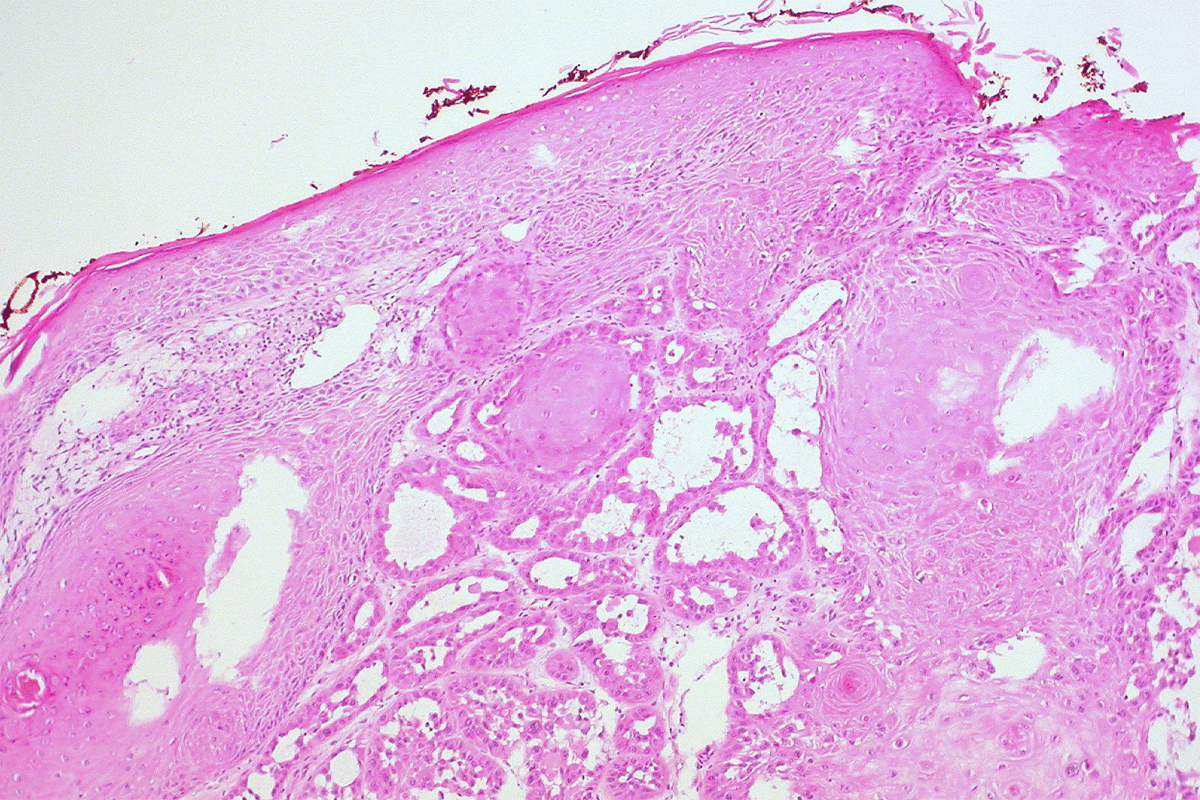

Inflammatory Conditions Like Lichen Sclerosis

Conditions like lichen sclerosis can also lead to strictures. They cause chronic inflammation and scarring. We help manage these conditions and prevent further issues, using treatments suited to each patient.